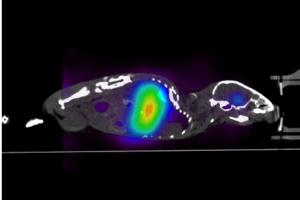

The Alpha-SPECT mini is a high-performance SPECT imaging system for preclinical research (mice and rats). It features high performance CZT sensors providing an unparalleled energy resolution. The scanner offers an ultra-wide stationary FOV to allow for TRU whole-body dynamic scanning of both mice and rats. This allows for imaging up to 4 mice simultaneously. This is a first in its class SPECT scanner with exceptional sensitivity, resolution, and many unique features.

TRUE whole-body dynamic mouse and rat studies

What and Why: Alpha-SPECT Mini™